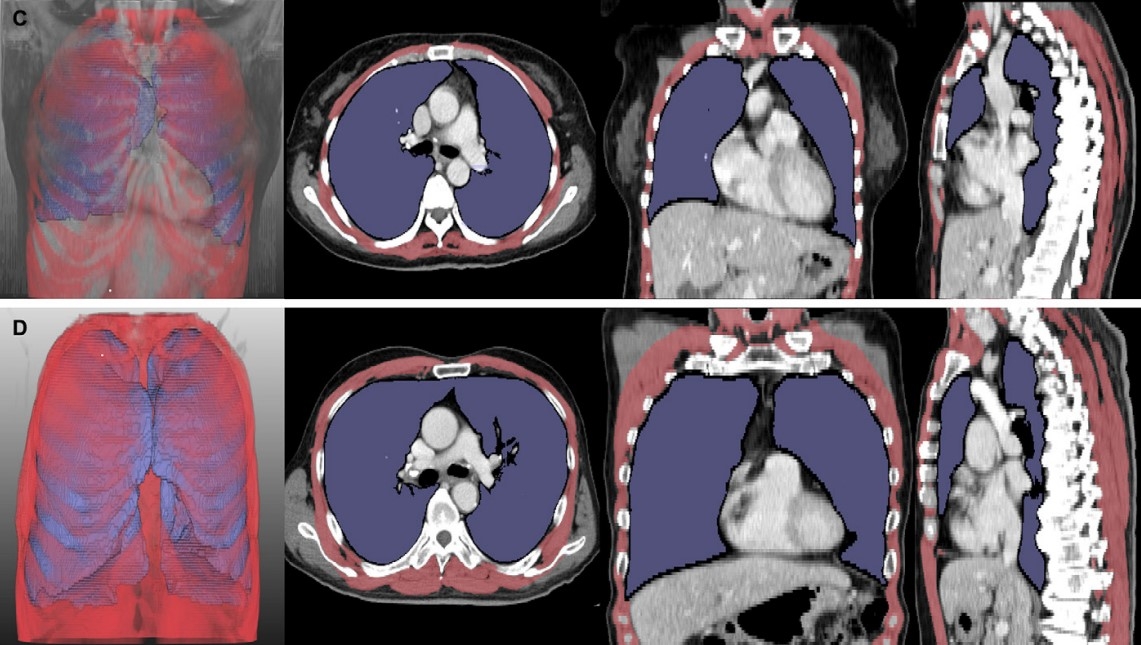

스포츠토토 환자의 흉부 CT 분석 결과.

[헤럴드경제=김태열 건강의학 선임기자] 스포츠토토 환자의 호흡 기능 평가는 주로 폐활량 검사를 통해 이뤄지지만, 구강안면 근육이 약한 환자는 검사 정확도가 떨어진다. 이에 서울대병원 연구팀은 딥러닝 기술로 흉부 CT 영상에서 폐와 호흡근 부피를 분석해 새로운 검사 지표를 개발했다. 이 영상 기반 지표는 스포츠토토 병기 및 생존 기간과 유의한 상관관계가 있는 것으로 나타나, 기존 검사의 한계를 보완할 수 있을 것으로 기대된다.

서울대병원 신경과 최석진·성정준 교수(김종수 전문의) 및 영상의학과 박창민·최규성 교수 공동 연구팀은 스포츠토토 환자 261명의 흉부 CT 영상을 분석해 이 같은 사실을 확인했다고 23일 발표했다.

이에 연구팀은 딥러닝 소프트웨어를 이용해 스포츠토토 환자의 폐와 호흡근 위축 정도를 나타내는 폐 용적 지수(LVI)와 호흡근 용적 지수(RMI)*를 개발하고, 병기 및 생존 기간과의 연관성을 확인했다.

그 결과, 폐·호흡근 용적 지수는 병기(1~4기)가 증가할수록 유의미하게 감소했다. 또한, 이 지수들이 낮은 그룹은 높은 그룹 대비 폐와 호흡근 위축이 뚜렷한 것으로 나타나, 기관절개술 또는 사망에 이르는 시점이 빨랐다.

또한, 통계 분석에 따르면 폐·호흡근 용적 지수는 기존 폐활량 검사와 유사한 정확도로 환자의 예후를 평가할 수 있었다. 이 결과는 구음장애 환자만 분석한 경우에도 동일하게 나타나, 연구팀이 개발한 영상 기반 지표가 호흡 기능을 평가하기 어려운 스포츠토토 환자에서도 폐활량 검사를 대체할 수 있는 가능성을 보여줬다.